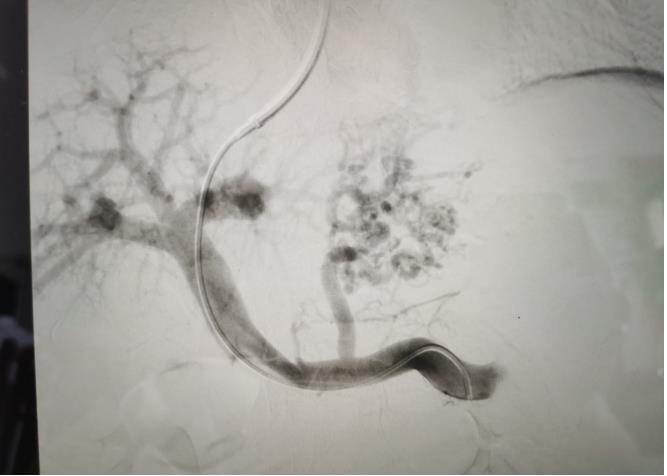

經(jīng)過(guò)我院血管介入科醫(yī)療團(tuán)隊(duì)的精心準(zhǔn)備,患者在數(shù)字減影血管造影機(jī)(DSA)導(dǎo)引下,順利經(jīng)頸靜脈入路進(jìn)入下腔靜脈并成功穿刺了門(mén)靜脈右支主干,術(shù)中栓塞了曲張的胃冠狀靜脈-食管靜脈叢將支架植入肝實(shí)質(zhì)內(nèi),支架兩端分別置于門(mén)靜脈和肝靜脈內(nèi),術(shù)程歷時(shí)2小時(shí),術(shù)中患者時(shí)刻保持清醒,手術(shù)切口僅5毫米,術(shù)后第2天恢復(fù)飲食,腹脹、腹水癥狀明顯好轉(zhuǎn),未出現(xiàn)嘔血、黑便及肝性腦病等并發(fā)癥,術(shù)后第3天康復(fù)出院。